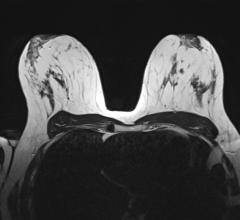

June 6, 2024 — Subsequent rounds of abbreviated breast MRI (AB-MR) screening in patients with dense breasts had lower ...